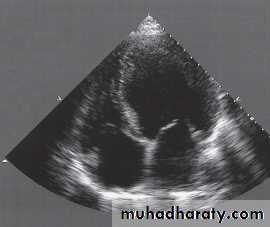

Echocardiography

Usually done after reperfusion therapy

Can be performed at the bedside

Useful to assess the status of the LV & RV

Detects mechanical complications

LV mural thrombus

Ventricular septal rutpture

Mitral regurgitation

Pericardial effusion

RV infarction